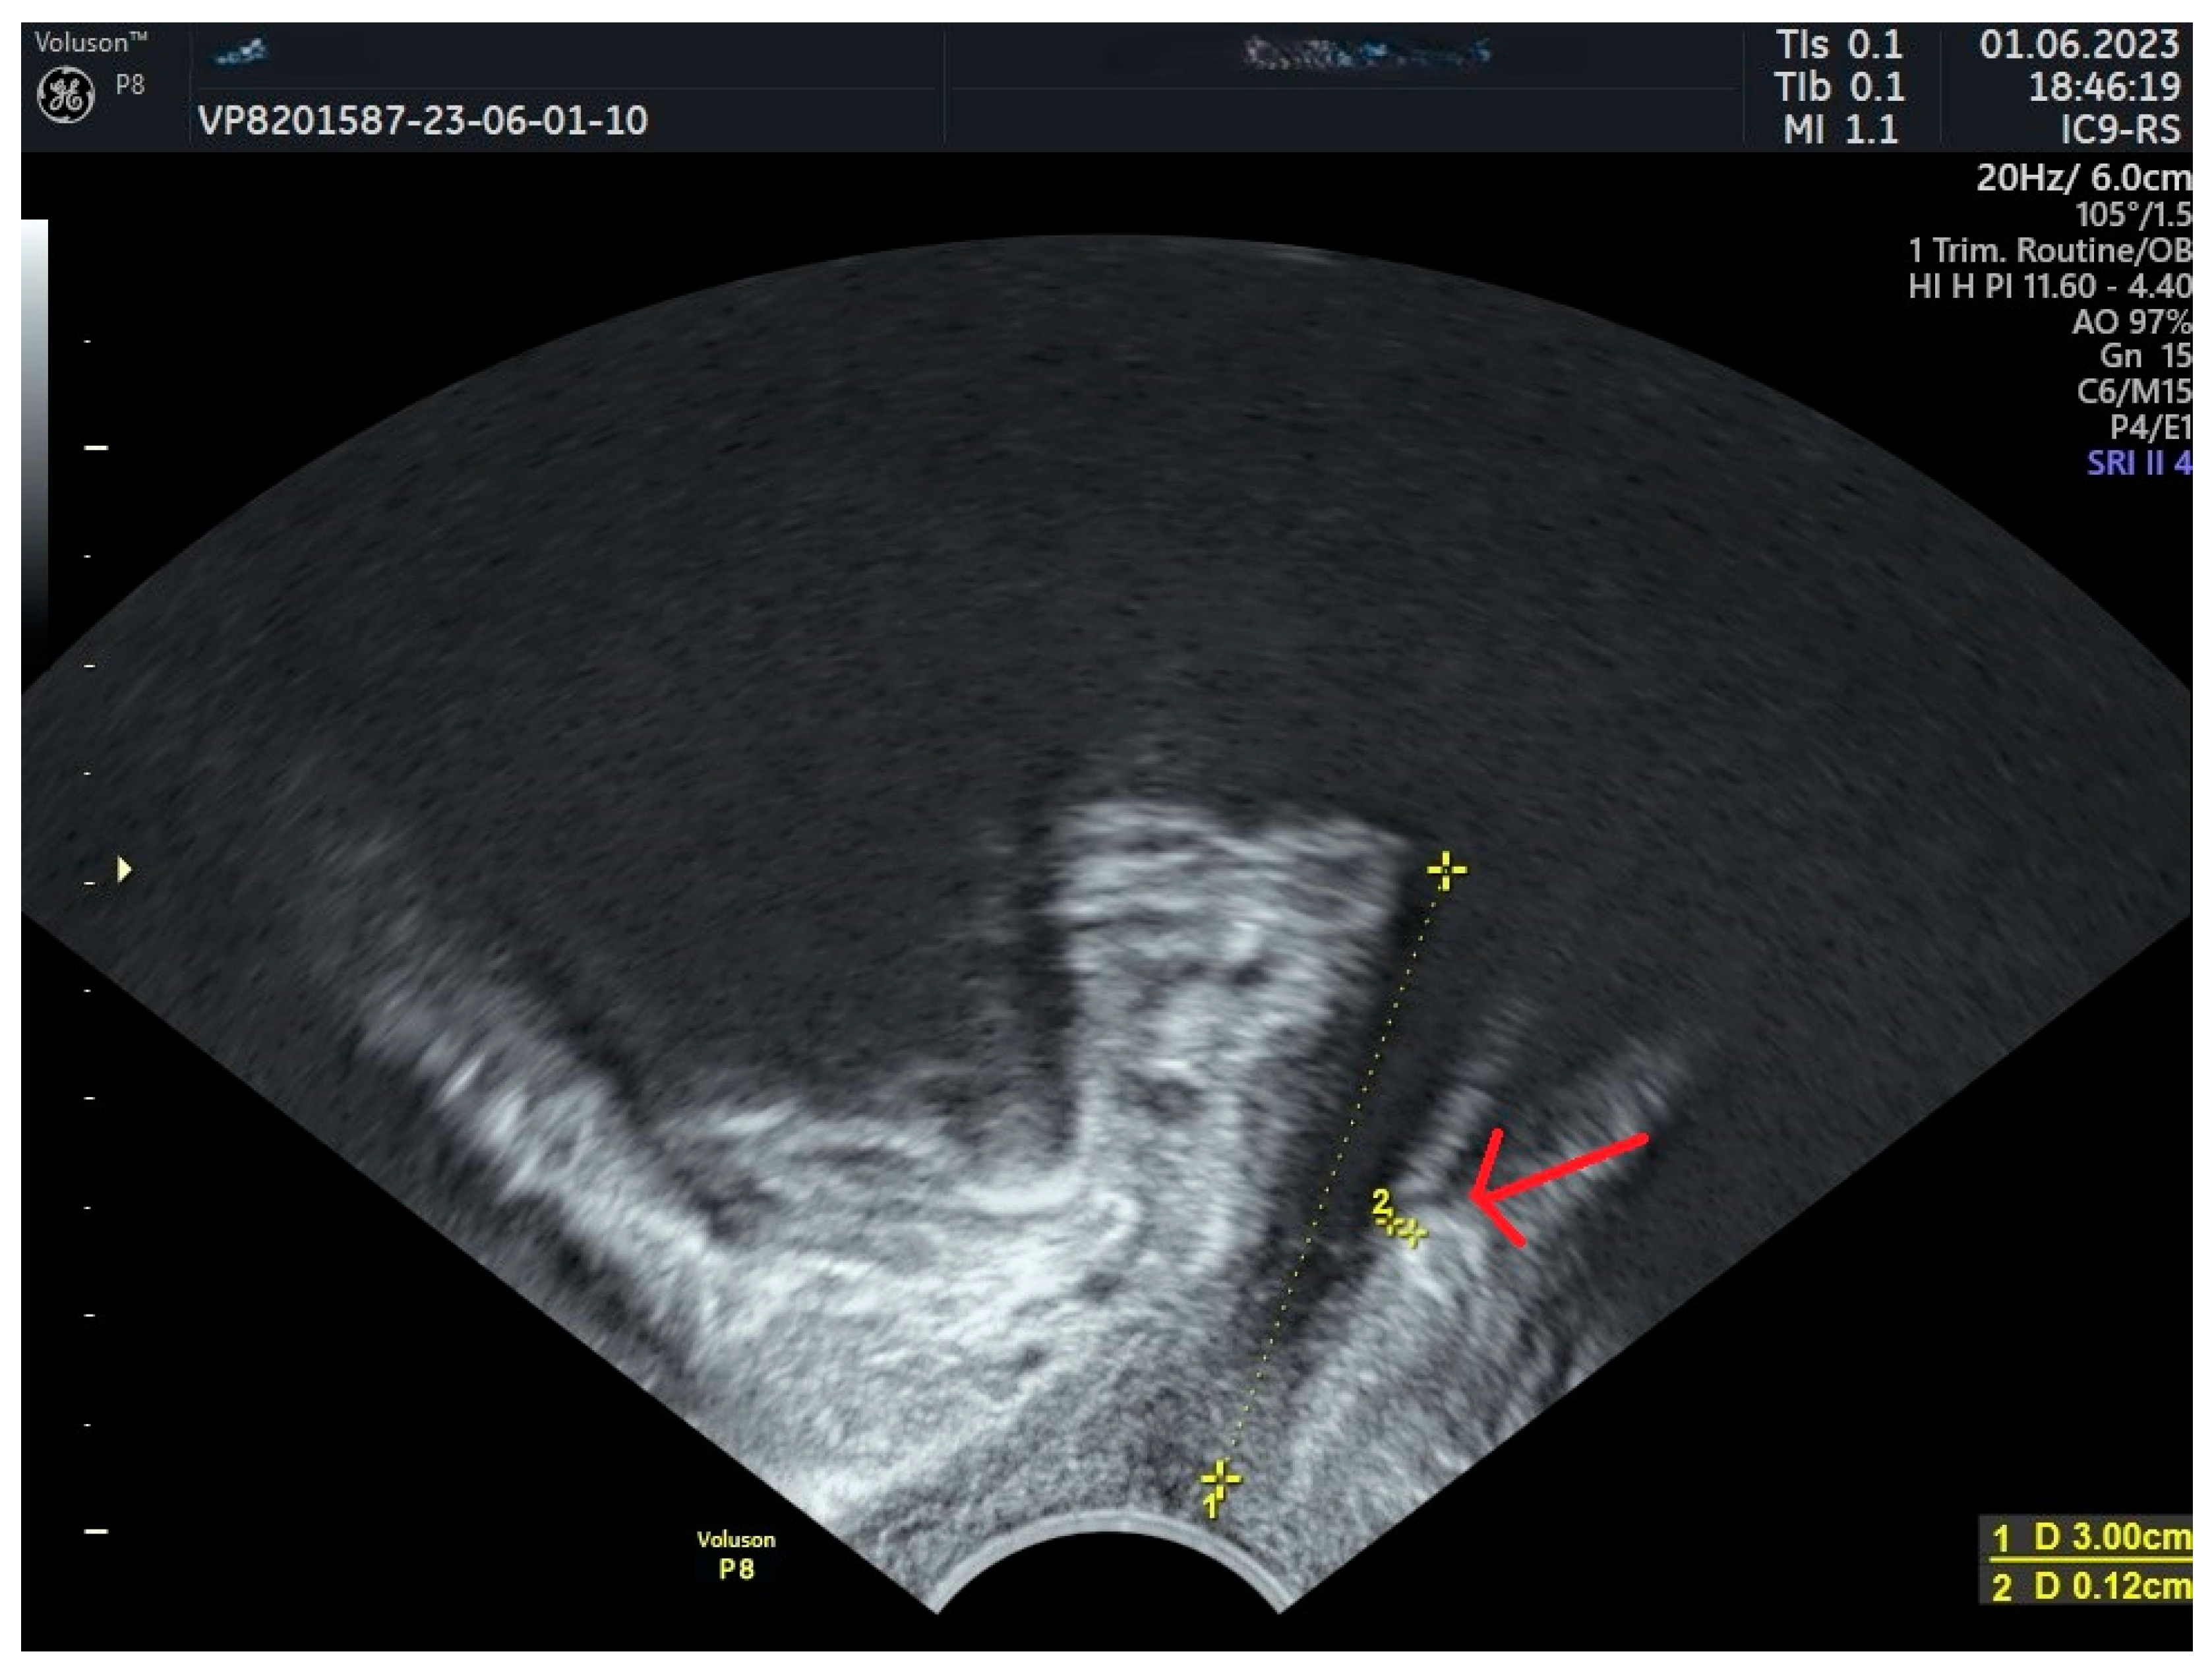

| Urinary Retention and obstructive voiding | Kociszewski et al., 2017 [35] | Median sling-LSM distance = 1.1 mm in the affected patients. |

| Reich et al., 2009 [67] | Tape-urethra distance < 2 mm in the affected patients. | |

| Viereck et al., 2013 [68] | Median sling-SLM distance = 1.5 mm. | |